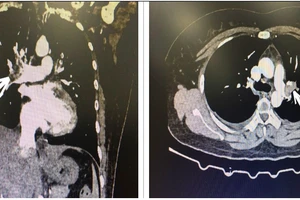

Đột ngột khó thở, cụ bà ngưng tim do nhồi máu phổi

Uống 12-15 viên thuốc tránh thai khẩn cấp mỗi tháng, người phụ nữ bị nhồi máu phổi